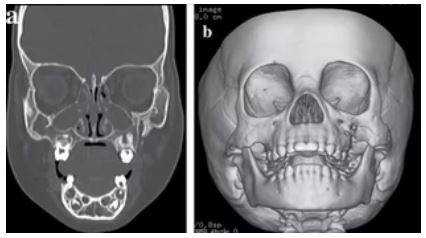

КТ лицевого черепа с 3D-реконструкцией

КТ лицевого черепа позволяет оценить:

Большинство повреждений головы сопровождается переломами костей лица и их смещением. Лицевой череп образуют лобные, челюстные кости и ряд мелких костей. Повреждение мелких костей лицевого черепа не всегда удается визуализировать при проведении обычного рентгена, наиболее информативно КТ лицевого черепа. Немаловажно отметить, что компьютерная томография позволяет диагностировать опухоли из хрящевой и костной ткани даже на ранней стадии. На снимках КТ лицевого черепа хорошо прослеживаются контуры опухоли, а также их прорастание в пространство мозгового черепа, носовую полость и глазницу. В таких ситуациях может потребоваться дополнительное внутривенное контрастирование.